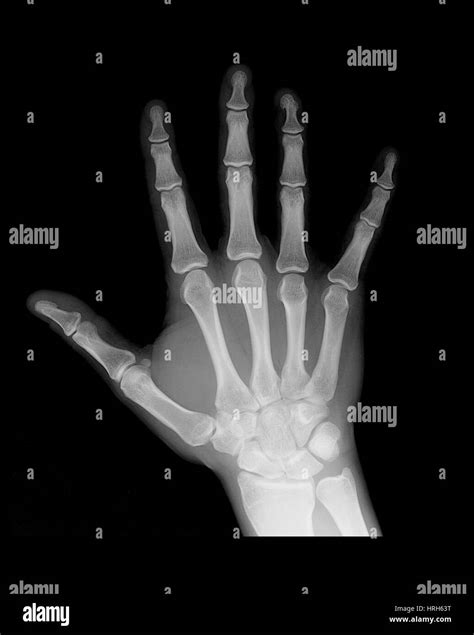

When you visit a medical imaging department after a sudden injury or persistent discomfort, the first step in diagnosing your hand is almost always a diagnostic imaging scan. Seeing an X Ray Normal Hand is often the baseline that radiologists use to compare against potential fractures, dislocations, or soft tissue irregularities. Understanding what a healthy hand looks like on a radiograph can help patients feel more at ease and better understand the information their healthcare provider is sharing. Whether you are dealing with a minor sprain or just curious about anatomy, the standard radiographic projection of the hand provides a wealth of information about the structural integrity of your bones and joints.

The human hand is a marvel of biological engineering, consisting of 27 individual bones. When a technician captures an X Ray Normal Hand, they are looking for specific structures that demonstrate proper alignment and density. The hand is broadly divided into three main sections, all of which are clearly visible on a standard radiographic projection:

• Carpals: The eight small, irregular bones that make up the wrist (carpus). These act as a bridge between the forearm bones and the hand.

• Metacarpals: The five bones that extend through the palm of the hand. These are numbered I through V, starting from the thumb.

• Phalanges: The bones of the fingers. Each finger consists of three phalanges (proximal, middle, and distal), while the thumb contains only two.

In a healthy, asymptomatic individual, these bones show smooth cortical edges, clear joint spaces, and no evidence of fragmentation. Radiologists examine these components to ensure there are no subtle hairline fractures or signs of chronic degeneration that might be mistaken for normal aging.